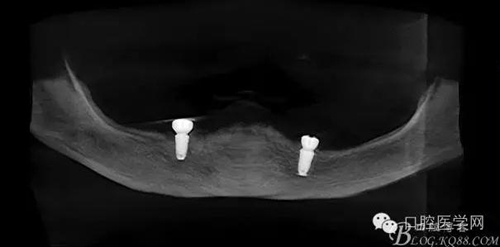

種植覆蓋全口義齒3個月后上球型基臺

種植覆蓋全口義齒下頜牙槽嵴吸收嚴(yán)重,若沒有種植體無法固位。